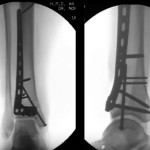

Pilon fractures- Anterior Approaches by Saqib Rehman MD- Part 2

Courtesy: Saqib Rehman MD Director of Orthopaedic Trauma Temple University Philadelphia Pennsylvania, USA www.orthoclips.com

Pilon fractures: Injury patterns and Surgical Planning by Saqib Rehman- Part 1

Courtesy: Dr Saqib Rehman MD Director of Orthopaedic Trauma Temple University, Philadelphia, Pennsylvania, USA